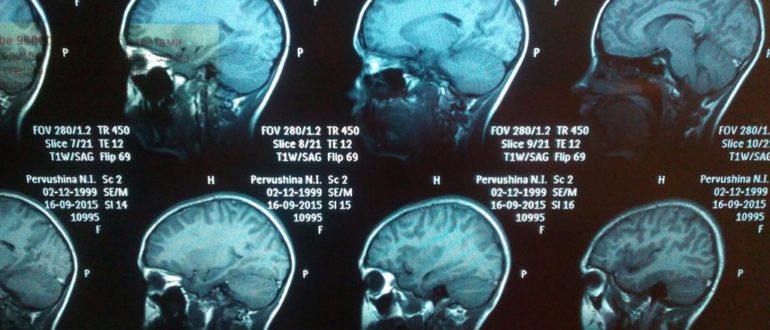

МРТ головного мозга (расшифровка)

Расшифровка МРТ головного мозга: результаты и заключение, норма у здорового человека Магнитно-резонансная томография – сложная, но точная диагностика, превосходящая и рентген, и УЗИ, и другие виды обследования. Однако…